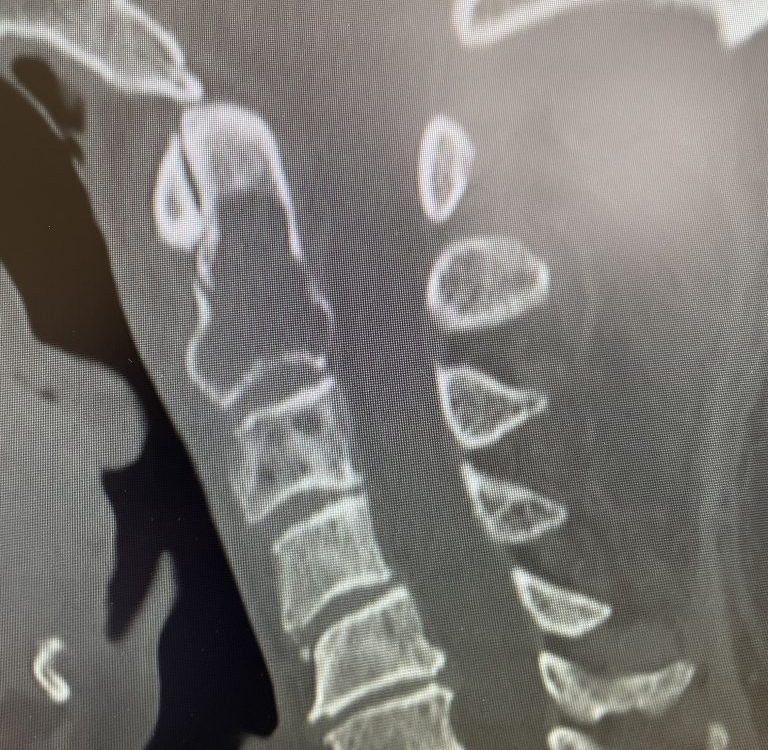

Here is a tough case: This is a 72 year-old male who presented with several months of progressive neck pain without symptoms of the arms or legs. […]